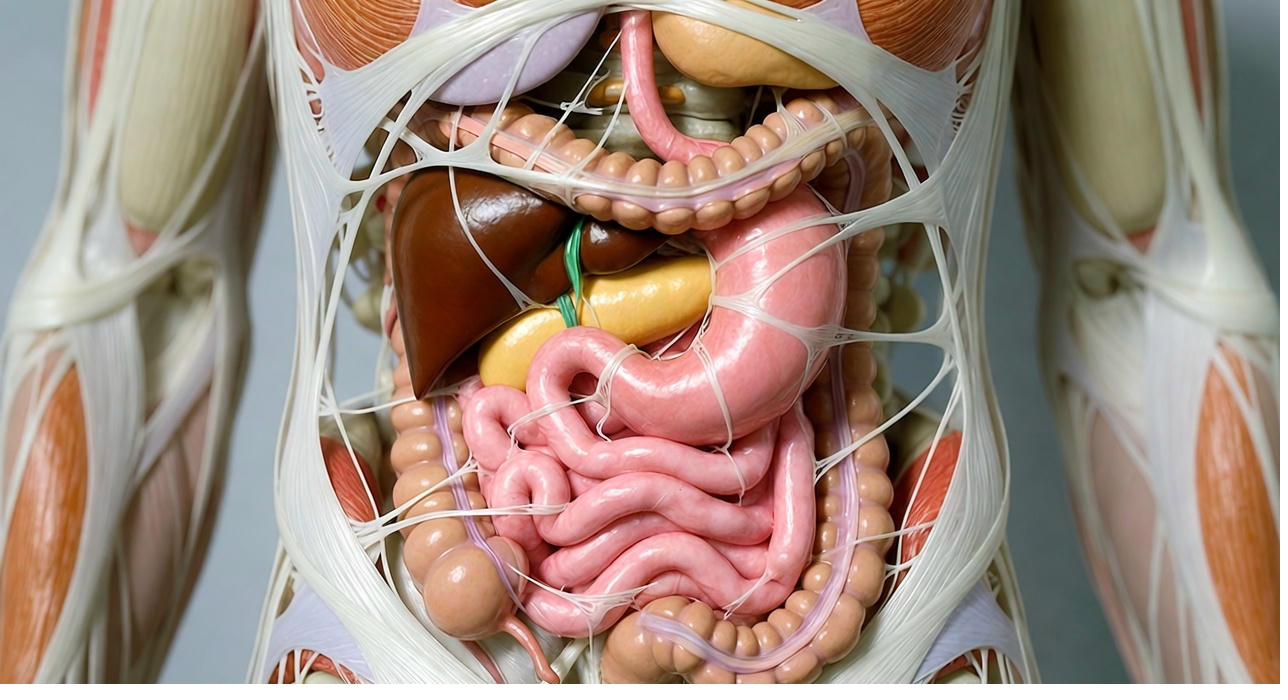

Fascia is your body's living, continuous web of connective tissue. It wraps every single muscle fibre, every nerve, every bone, every organ, forming one uninterrupted three-dimensional network from head to toe. It's richly supplied with nerves and plays an active role in how your body feels and moves.

When Fascia becomes unhealthy, through injury, poor posture, repetitive strain, or chronic stress, the tissue dehydrates, thickens, and forms Fascia adhesions. Sticky spots where layers that should slide now grip and pull.

This pull doesn't stay in one spot. Because Fascia is interconnected, tension travels along the web. A restriction in your lower back can tug on your neck, shoulders, hips, even your hands, creating pain that seems to come from nowhere.

Researchers have found that the classic "tender points" used to diagnose Fibromyalgia are, in fact, active Myofascial Trigger Points. When these points are stimulated, they reproduce the entire spontaneous pain pattern of Fibromyalgia patients, not just local pain.